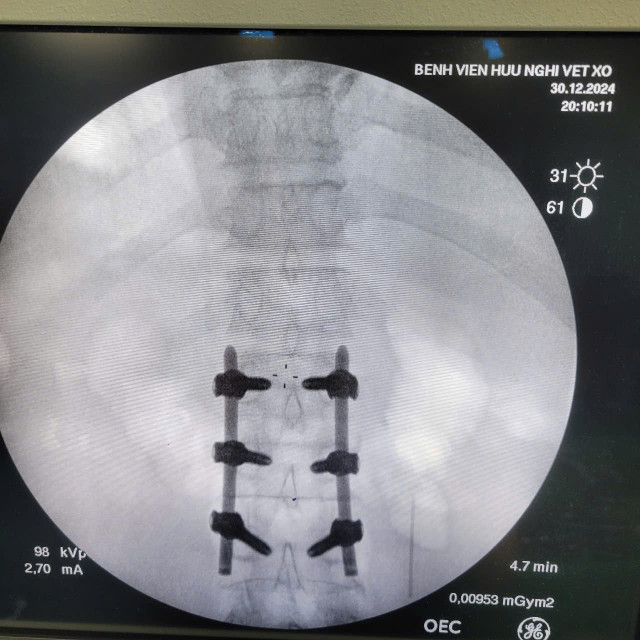

Các bác sĩ Khoa Ngoại Thần kinh – Chấn thương Chỉnh hình, Bệnh viện Hữu Nghị đã triển khai thành công kỹ thuật mới, phẫu thuật bắt vít cột sống qua da ít xâm lấn cho bệnh nhân nam 59 tuổi bị chấn thương cột sống, vỡ đốt sống L2 gây mất vững.

Sử dụng hệ thống máy C-arm, dẫn đường hình ảnh (navigation) để đặt vít chính xác tuyệt đối, tránh tổn thương tủy sống và rễ thần kinh.